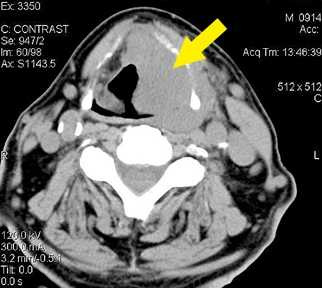

Благодаря своему расположению и строению, щитовидка хорошо просматривается и пальпируется. На фото 1 можно визуально увидеть, как она выглядит и где расположена.